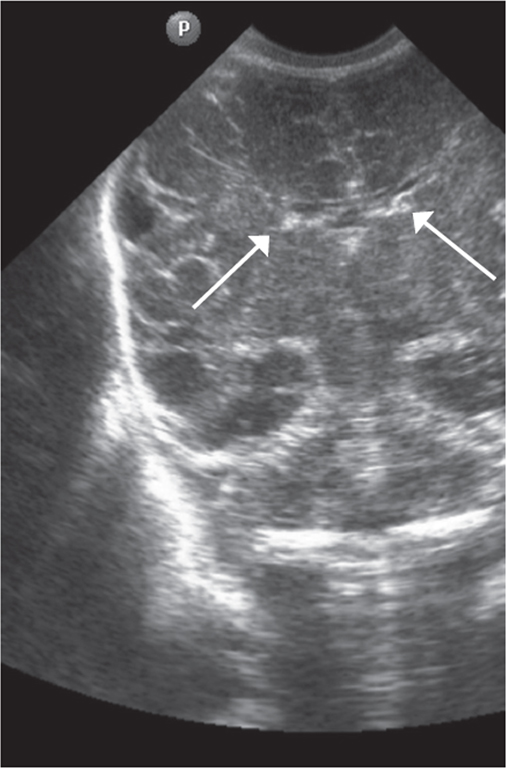

Методом КСГ субэпендимальный герминальный матрикс может определяться до 29 недель включительно в виде гиперэхогенных участков в переднем отделе бокового желудочка (в проекции отверстия Монро) [7, 8, 13]. Герминальный матрикс на МРТ визуализируется до 30 недель гестации при выполнении спин-эховых последовательностей Т1 и Т2 в виде гипоинтенсивного сигнала на Т2 ВИ и гиперинтенсивного сигнала Т1 ВИ в области каудальной вырезки вдоль стенки бокового желудочка [10].

Краниальная сонография выполнена всем новорожденным (4 недоношенным новорожденным 25 недель гестации, 5 недоношенным 26 недель гестации, 3 недоношенным новорожденным 27, 28, 29 недель гестации) по общепринятой методике через большой родничок с использованием микроконвексного и линейного датчиков (5–7 Гц), аппарат Philips HD11 [14]. Методом КСГ проведено измерение визуализируемого гериминального матрикса в передних отделах боковых желудочков (проекция отверстия Монро), определяли толщину герминального матрикса, единицы измерения представлены в миллиметрах (мм) системы СИ (рис. 1).

Рис. 1. Краниальная сонография недоношенного новорожденного, 28 недель гестации, фронтальный скан. Стрелками указаны области визуализации герминального матрикса

Fig. 1. CUS image of preterm newborn, gestational age 28 wks., frontal scan. Arrows indicate the area of visualization of the germinal matrix

В ПКВ 30 недель герминальный матрикс методом КСГ не определялся. Рис. 3 демонстрирует ультразвуковую картину головного мозга с отсутствием визуализации герминального матрикса в просвете передних отделов боковых желудочков (недоношенный ребенок ПКВ 30 недель).

Рис. 3. Краниальная сонография недоношенного ребенка 30 недель ПКВ. Фронтальный скан. Герминальный матрикс в просветах передних отделов боковых желудочков не визуализируется

Fig. 3. CUS image of preterm newborn, gestational age 30 weeks, frontal scan. The germinal matrix is not visualized

Исследование показало, что субэпендимальный герминальный матрикс боковых желудочков выявляется ультразвуковым методом у всех недоношенных новорожденных группы исследования до 29 недель гестации включительно (100 %). По данным K. Buch, герминальный матрикс визуализируется в виде гиперэхогенной структуры только у 13 % детей до 29 недель гестации [2]. Нами выявлена регрессивная динамика сонографической визуализации герминального матрикса у всех недоношенных новорожденных с ЭНМТ с увеличением гестационного возраста. Значительное сокращение размеров герминального матрикса по результатам КСГ наблюдается у недоношенных новорожденных с ЭНМТ к 29 неделям гестации.

Подтверждается возможность использования ультразвуковых методов, а именно КСГ, в оценке паттернов нейропластичности/регрессии герминального матрикса у недоношенных новорожденных. Герминальный матрикс КСГ визуализируется у всех недоношенных новорожденных до 29 недель гестации. Наблюдается регрессия герминального матрикса с максимальным снижением визуализации к 29 неделям гестации.